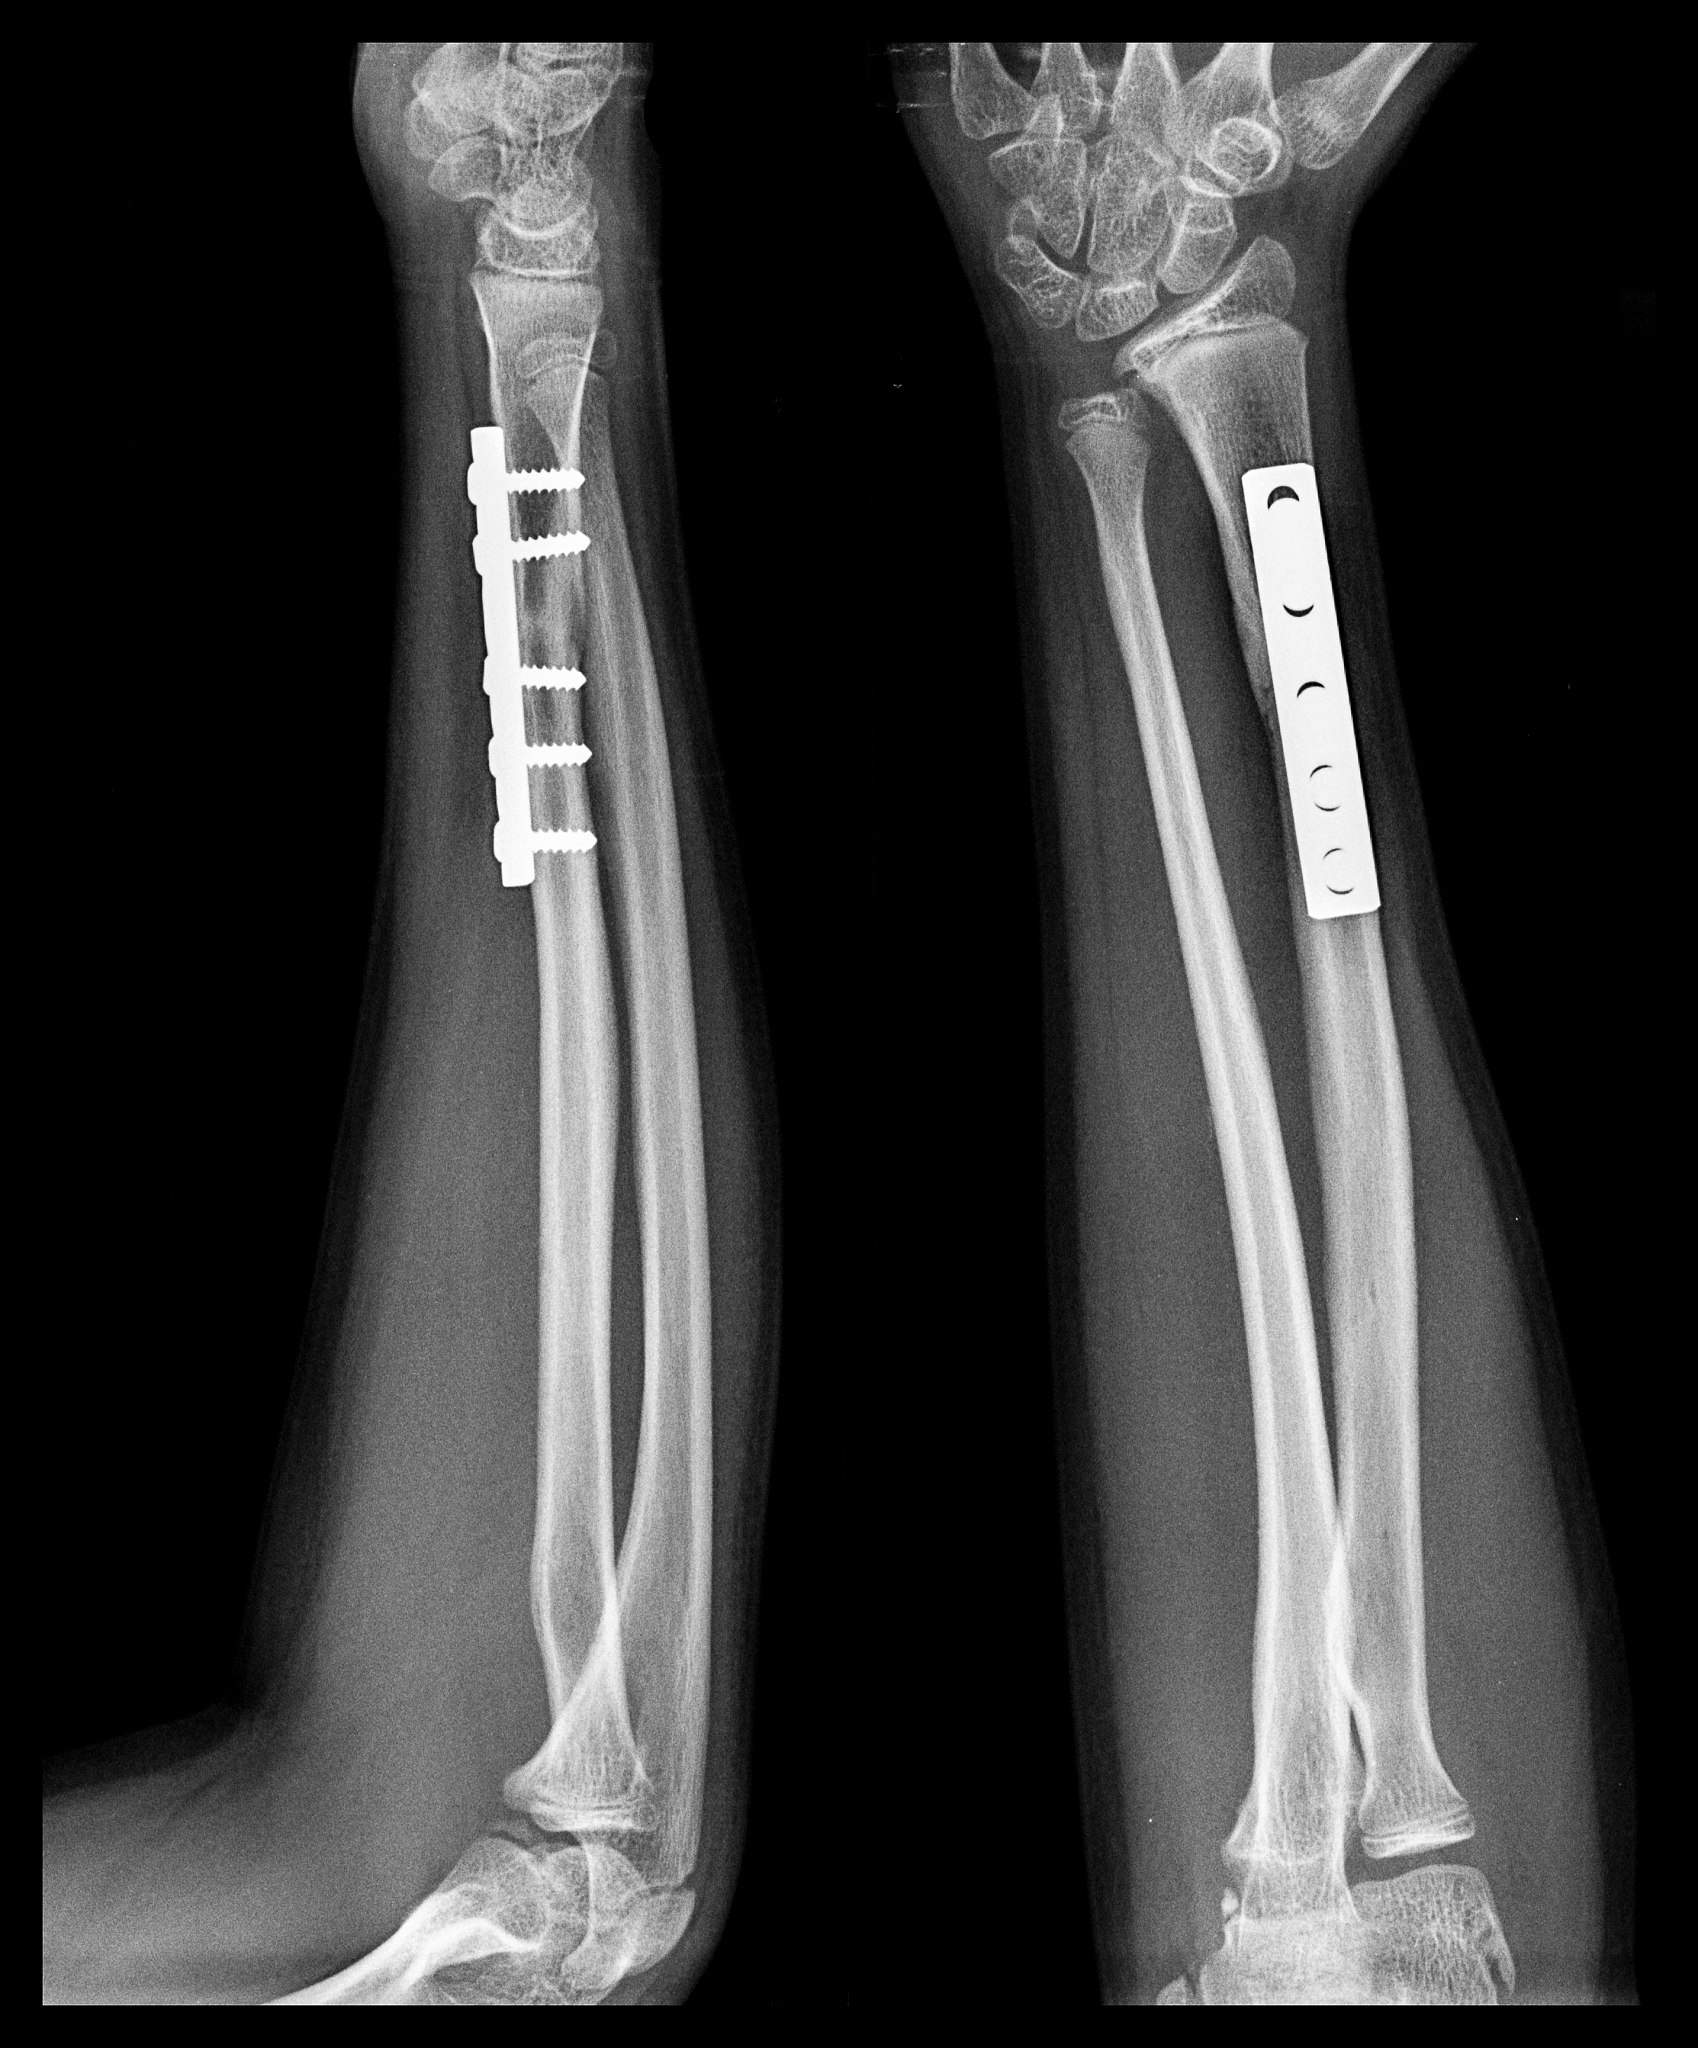

4. 接下来,医生会使用金属板和螺钉将骨折部位固定。金属板和螺钉的选择和安放位置会根据患者的具体情况而定。

5. 完成固定后,医生会进行术后的X射线检查,以确保骨折部位得到了正确的复位和固定。